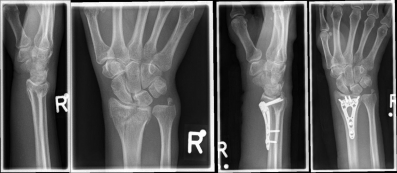

Handgelenk 1Often the inspection of the wrist already shows a suspected diagnosis. The accident mechanism must be clarified and after the physical examination, X-ray images of the wrist must be made in 2 levels.

In the classification of the distal radius fractures, the position of the fracture as well as a possible involvement of the articular surface are considered. Furthermore, the accident mechanism allows a classification of the fractures: the fall on the outstretched hand leads to a so-called extension fracture (Colles fracture), while the fall on the bent hand leads to a flexion fracture (Smith fracture).

Handgelenk 2The most common classification according to the Association for Osteosynthesis in fractures without involvement of the articular surface (A-fracture), fractures with partial joint involvement (B-fractures) and fractures with complete joint involvement (C-fracture). This results in indications for the therapeutic procedure.

Handgelenk 3

Pictures: A distal radius fracture with joint involvement (C-fracture) was treated with a plate osteosynthesis. After surgery, the plaster can be removed and physiotherapy exercises can be performed.